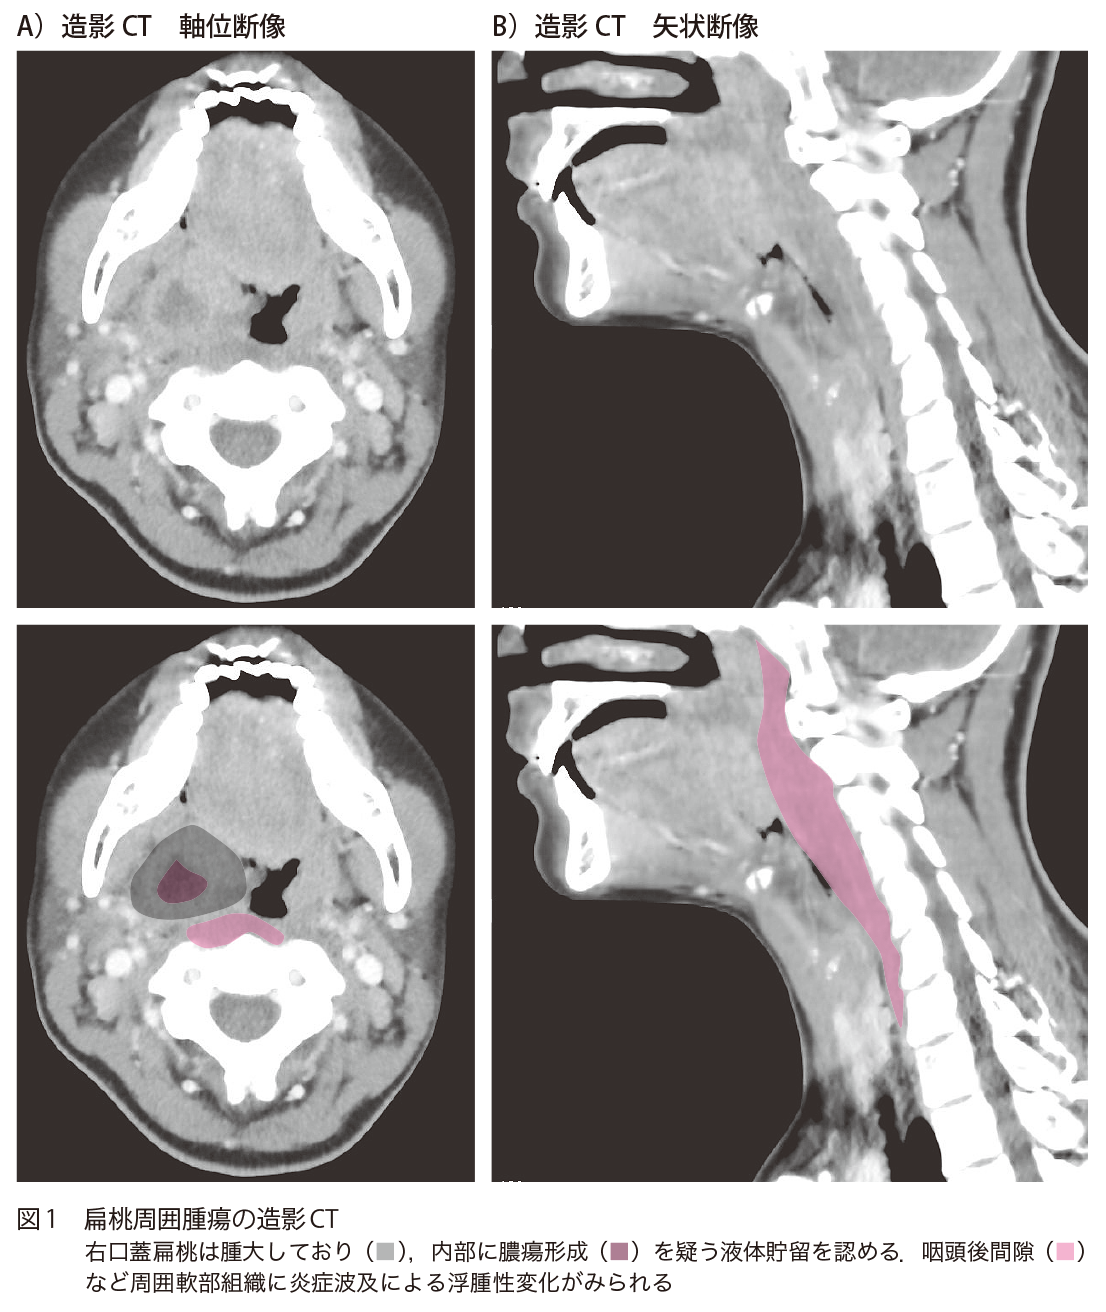

咽頭痛,特に開口時痛著明な20歳代女性 20歳代女性,2カ月前から咽頭痛,扁桃腫大にて近医を受診.抗菌薬などで症状はいったん改善していた.1日前から咽頭痛が再燃し,本日咽頭痛の増強,特に開口時痛著明で,救急外来受診となった. A1.右扁桃周囲膿瘍と咽頭後間隙の高度な浮腫性変化A2.扁桃周囲膿瘍 1.診断のポイント 1 造影CT所見 右口蓋扁桃は腫大しており,内部に膿瘍形成を疑う液体貯留を認める(図1).また,咽頭後間隙など周囲軟部組織に炎症波及による浮腫性変化がみられる. 2 扁桃周囲膿瘍 扁桃炎から生じる扁桃周囲に限局した膿瘍であり,発熱,咽頭痛,開口障害の症状を呈する.通常片側性であるが,両側性の報告1)もみられる.20~30歳代と比較的若年でみられることが多い. 口蓋扁桃下極側を中心とする下極型の扁桃周囲膿瘍では喉頭蓋を含めた声門上喉頭にしばしば進展し,気道狭窄/閉塞をきたす傾向があることから注意深い画像診断と臨床評価が必要となる.通常の上極よりの膿瘍と比較して経口的排膿が困難な場合がある点も臨床的に重要である. 参考症例:扁桃周囲膿瘍 下極型 40歳代男性,呼吸困難を訴え,近医受診し,ステロイド点滴されるも,酸素化低下,呼吸停止があり,救急搬送となった. 心肺停止蘇生後,気道確保後に撮影された造影CT(図2)では喉頭蓋を含めた声門上喉頭の著明な浮腫性変化,腫大がみられる.左口蓋扁桃下極に膿瘍形成がみられ,こちらからの炎症波及と考えられた. 2.鑑別診断 ■ 中咽頭癌(扁桃癌) 画像所見上は鑑別となるが,臨床経過などが異なるため,実臨床での鑑別は容易と思われる. 3.次の一手 造影CTにて膿瘍形成が明らかではない場合には抗菌薬投与などの内科的加療となり,膿瘍形成がある場合には周囲深部組織間隙への進展範囲評価にあわせて穿刺吸引あるいは切開排膿といった外科的治療を考慮し,耳鼻咽喉科医にコンサルテーションする. 救急医Check Point 急性喉頭蓋炎の場合と同様に,まず上気道閉塞の可能性があるかどうかについて評価し,吸気性喘鳴・起坐呼吸・チアノーゼなどの高度の気道狭窄症状1)を認め,酸素化が維持できない場合は診断よりもまず気道確保を優先する.気道確保においては経口での気管挿管が困難な可能性があるため,輪状甲状靱帯切開などの外科的気道確保ができる耳鼻咽喉科医,救急医,外科医や全身管理のできる麻酔科医などを招集し,気管挿管が失敗した場合に即座に外科的気道確保ができる体制を整えたうえで気道を確保する.その後,穿刺を行い,排膿を認めれば確定診断となる.得られた膿の培養に基づいて抗菌薬にて治療を行う.また,扁桃周囲膿瘍は解剖学的連続性1)から傍咽頭間隙膿瘍,咽後膿瘍,縦隔膿瘍に進展している可能性があり,その場合には扁桃以外に追加で放射線科によるCTガイド下でのドレナージや心臓血管外科,胸部外科による外科ドレナージが必要となるため,造影CTでそれらの膿瘍を認めた場合は当該科へのコンサルトが必要である. 文献:1)渡辺哲生:解剖から見た扁桃周囲膿瘍・深頸部膿瘍.口咽科,29:9-17,2016 文献・参考文献 海邊昭子,他:扁桃周囲膿瘍115症例の臨床的検討.日耳鼻,118:1220-1225,2015 「頭頸部の臨床画像診断学 改訂第3版」(尾尻博也/著),南江堂,2016 (2020/5/8公開) 戻る この"ドリル"の掲載書をご紹介します レジデントノート増刊 Vol.22 No.2画像診断ドリル救急医と放射線科医が伝授する適切なオーダーと読影法 藪田 実,篠塚 健/編 定価:4,700円+税 在庫:あり 月刊レジデントノート 最新号 次号案内 バックナンバー 連載一覧 定期購読案内 定期購読WEB版サービス 定期購読申込状況 レジデントノート増刊 最新号 次号案内 バックナンバー 定期購読案内 residentnote @Yodosha_RN その他の羊土社のページ ウェブGノート 実験医学online 教科書・サブテキスト 広告出稿をお考えの方へ 広告出稿の案内